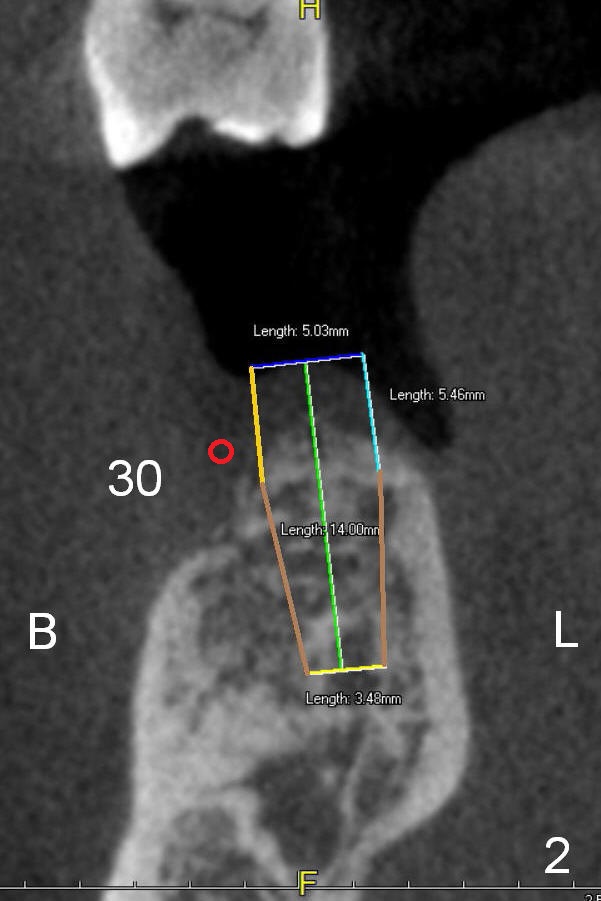

A 74-year-old man has lost the teeth #30 and 31 for a while. He is wearing a RPD and is not comfortable with it. CT analysis reveals that 5x14 and 6x14 mm implants could be placed at the site of #30 and 31, respectively (Fig.1 CT sagittal section), Fig.2,3 (coronal sections)). If implant threads are exposed, decorticate locally, place bone graft (Fig.2 red circle) and a piece of extended use collagen membrane (circling the implant, to be sutured first). If insertion torque is high for both implants, splint provisionals and minimal occlusal contact. For the best positioning, take Alginate impression when the patient returns for #8,9 implant placement.